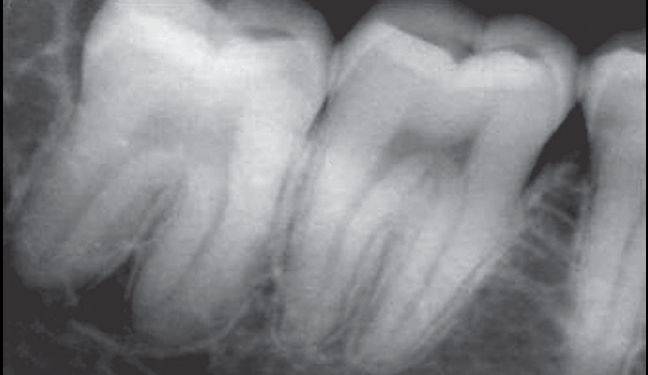

根部阻力亦可称根部骨阻力或牙根阻力。根部阻力主要根据X线片分析,阻力大小与牙位、牙根数目、牙根形态、根尖形态、根周骨组织情况有关。

根周骨阻力以骨质增生和牙根有骨粘连者阻力较大,根周骨质疏松、有炎症性骨吸收者阻力较小。